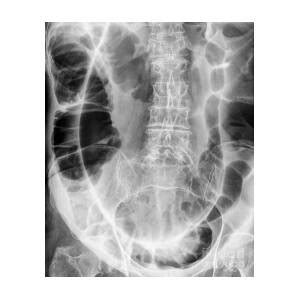

Twisted colon Stock Image M290/0118 Science Photo Library